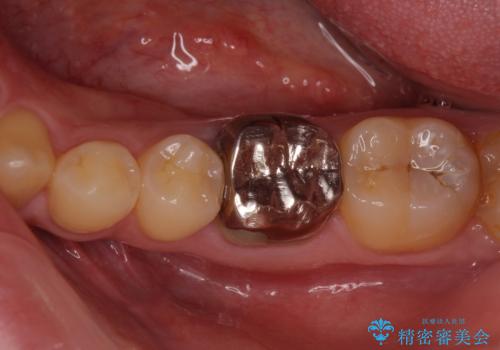

銀歯を白くしたい セラミックによる審美歯科治療

- 治療中の前歯と口腔内にある銀歯が気になるとのことで来院された患者様です。

土台に含まれている金属も含め、口腔内の金属は全て除去し、根管治療が必要な歯は根管治療を行い、オールセラミッククラウンやセラミックインレーにて治療することとしました。